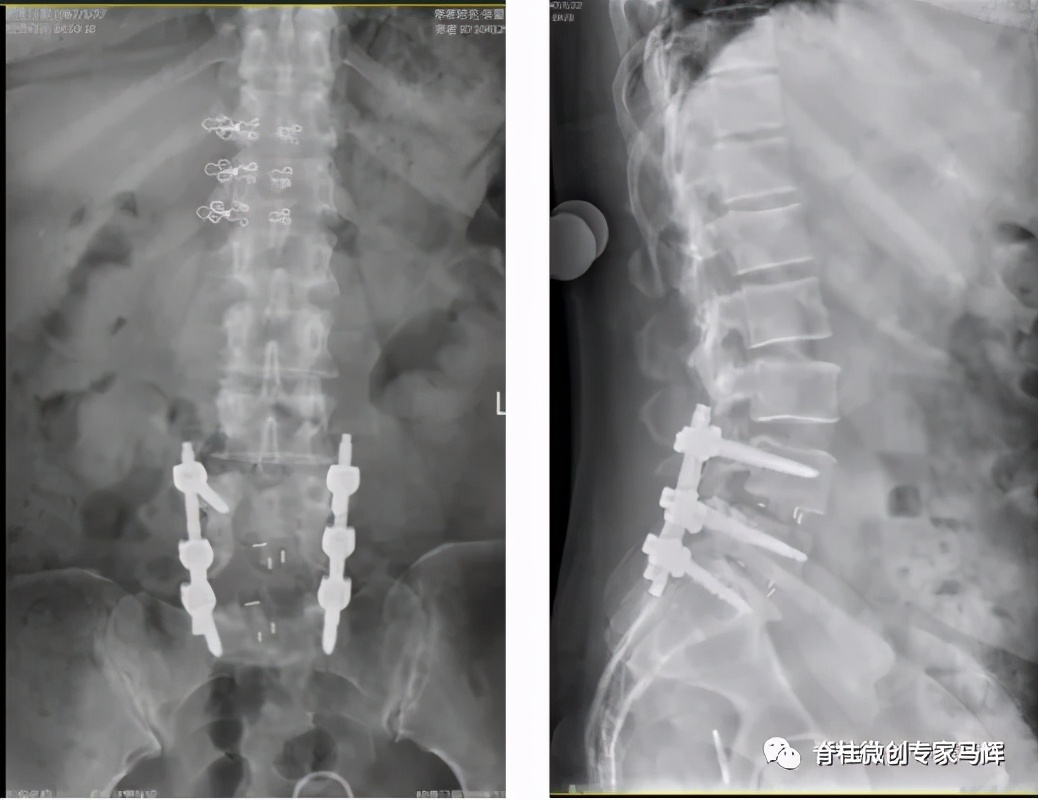

术后